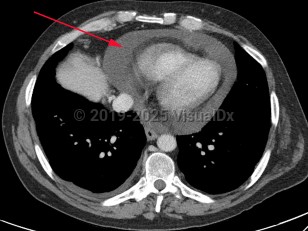

Aortic dissectionAortic dissection

Cardiac tamponadeCardiac tamponade

Pericardial effusionPericardial effusion